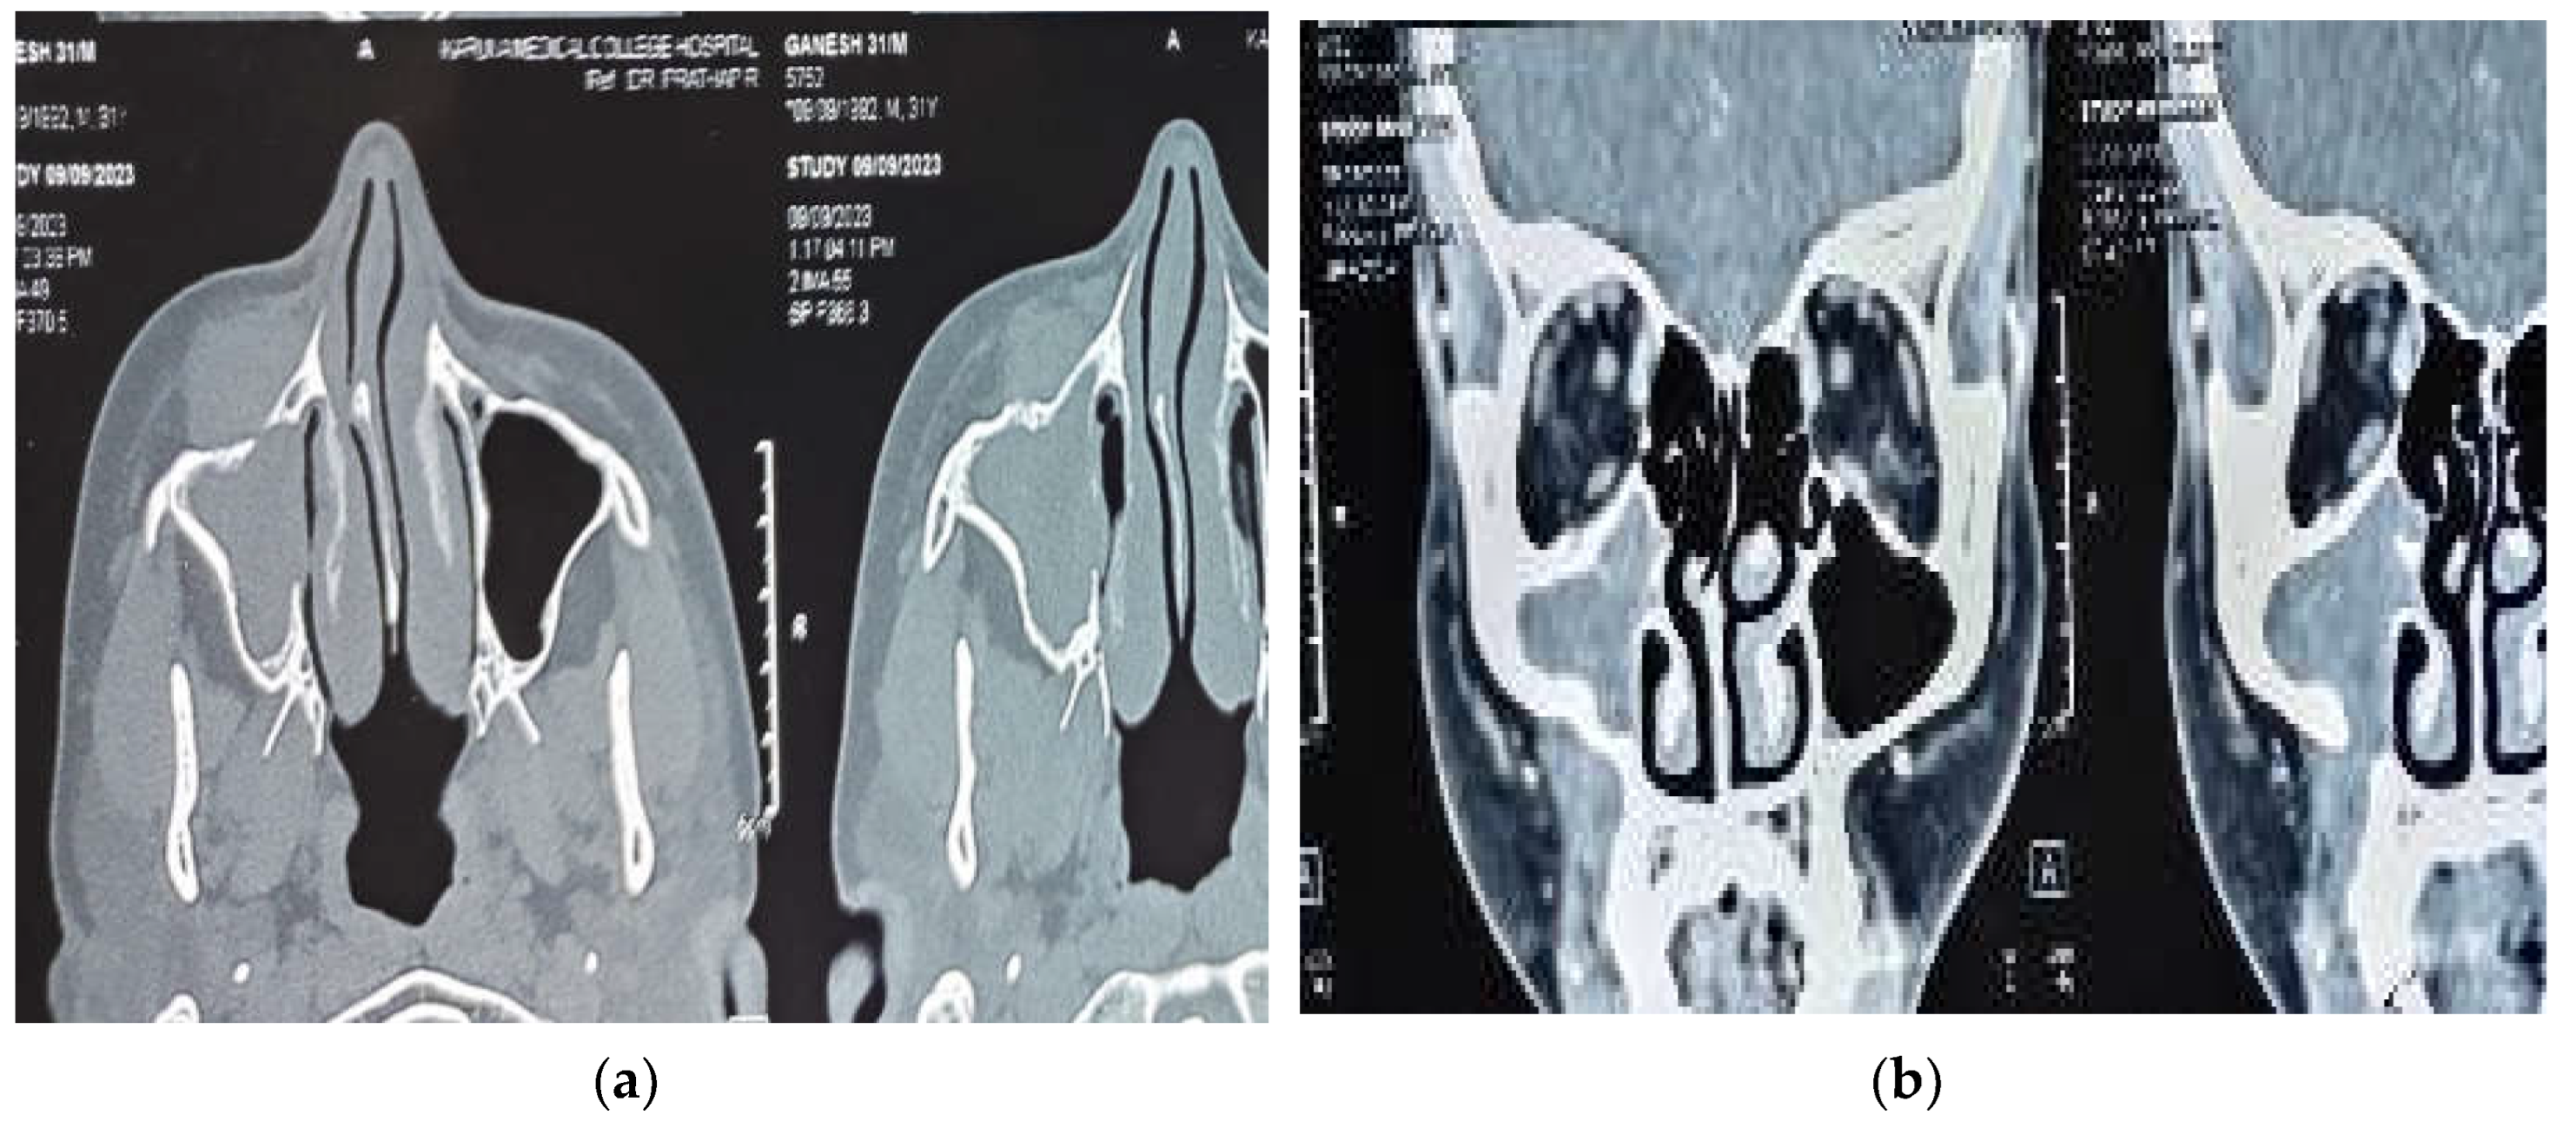

A diagnostic nasal endoscopy was performed and it showed deviation of the anterior nasal septum to right with a bony spur not touching the lateral wall. Non contrast computerized tomography of the nose and paranasal sinuses revealed partial opacification of the right maxillary sinus with partial erosion of the anterior maxillary wall. The lesion was found to be extending through a defect into the soft tissue over the premaxilla area without involving the subcutaneous fat planes. Post intravenous contrast administration, the lesion showed mild enhancement with bony scalloping and erosion of the right maxillary sinus and part of alveolar process of maxilla (Figure 1 (a) and 1 (b) ). As there was no involvement of orbit or intracranial extension a magnetic resonance imaging was not advised.

Figure 1. (a) Axial plain computed tomography of paranasal sinuses showing opacification of right maxillary sinus with erosion of anterior wall of maxilla. Presence of soft tissue density in the pre maxillary region also can be seen (b) Contrast enhanced computed tomography of paranasal sinuses (coronal section) showing heterogeneous soft tissue opacification of right maxillary sinus with bony erosion of anterior maxillary wall and extension of lesion into the anterior aspect of maxilla.

Radiological imaging gives hints which points towards the possibility of fungal etiology. Computed tomography is essential in identifying bone changes whereas MRI may give much more detailed information about soft tissue extensions. This is particularly of important in cases where orbit, sellar or intracranial extension is suspected. CT findings supporting the CFRS diagnosis are disease limited to few sinuses, bone erosion rather than necrosis or sequestrum formation and heterogeneous sinus mucosal thickening [17]. Because of this bone erosion causing property disease extension to adjacent regions is not uncommon. 7 out of 10 patients of Asoegwu et al had orbital extension, with 5 patients having intracranial and one patient with pterygopalatine fossa extension [14]. Similar aggressive nature of the disease was noted by Alarifi et al, where 5 out of 7 patients had orbital involvement, and two patients with intracranial extension [15]. The SARS Cov 2 co-existed case reported by Gonzalez et al also had extension into orbit as intraconal abscess [16]. However our patient had a localized involvement with minimal erosion of anterior maxillary wall and pre antral tissue infiltration without orbital involvement. This may be due to previous repeated treatments taken by the patient from outside where the underlying inflammation process is of less intensity. The bone erosion could be attributed to long standing pressure changes as no lytic or periosteitis changes where seen.